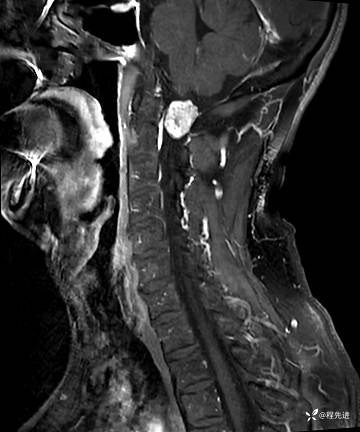

MRI平扫+增强:

T1: